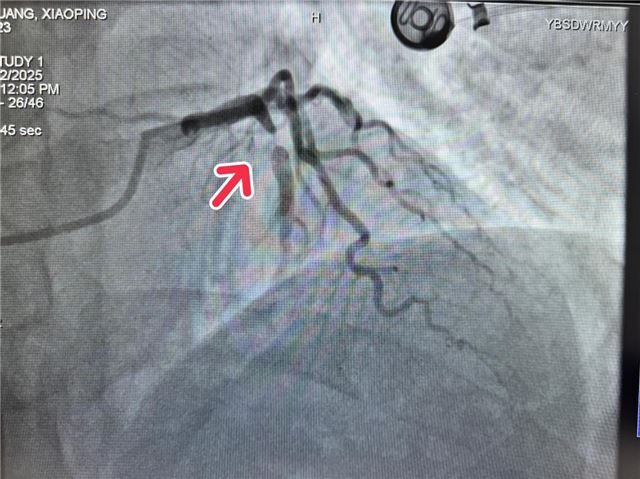

介入室胡前坤主任接到消息后远程指导给予急救药物和抗凝治疗,并提醒警惕恶性心律失常。话音刚落,患者突发抽搐、意识丧失,陷入昏迷状态,监护仪警报响起:室颤!这是心梗最危险的并发症,心跳骤停随时可能发生。介入室、急诊科、老年病科医护人员立即联合施救——心肺复苏、200J电除颤……紧张有序的急救之后,患者意识恢复,初步抢救成功!随后,团队迅速为患者施行急诊介入手术,成功开通闭塞血管,恢复血流,将患者从死亡边缘拉回。